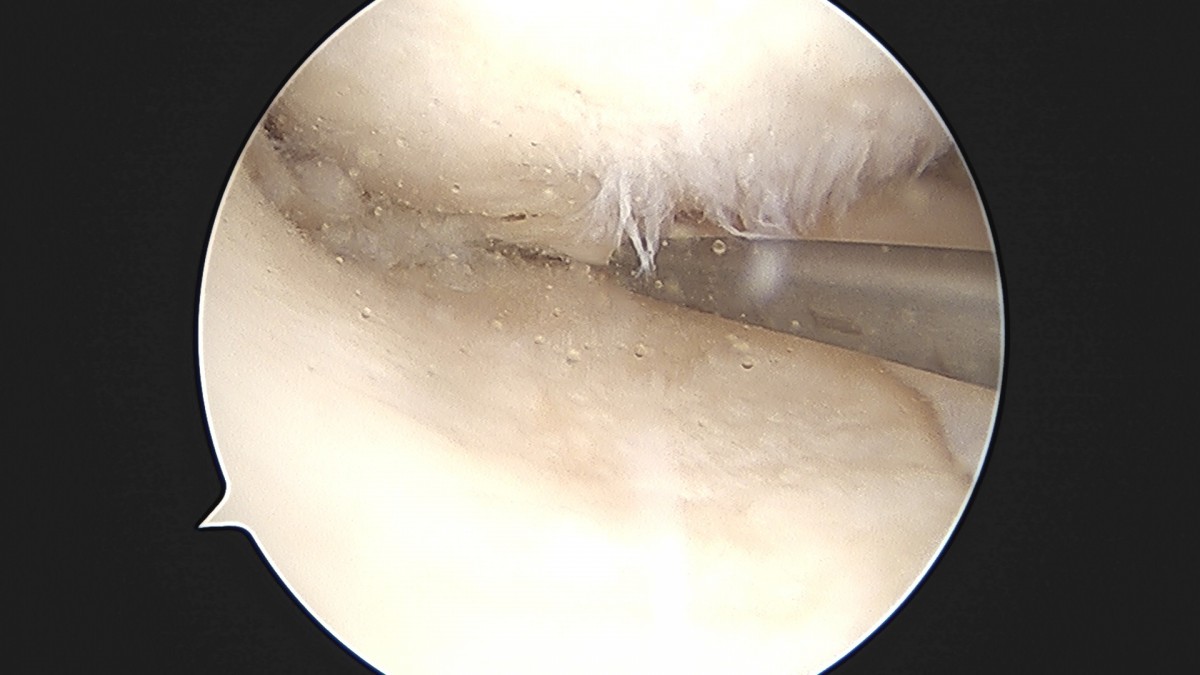

이재상원장님 무릎 반월상 연골판 절제술 박민O 환자

작성자 최고관리자 댓글 0건 조회 382회 작성일 25-09-16 15:46